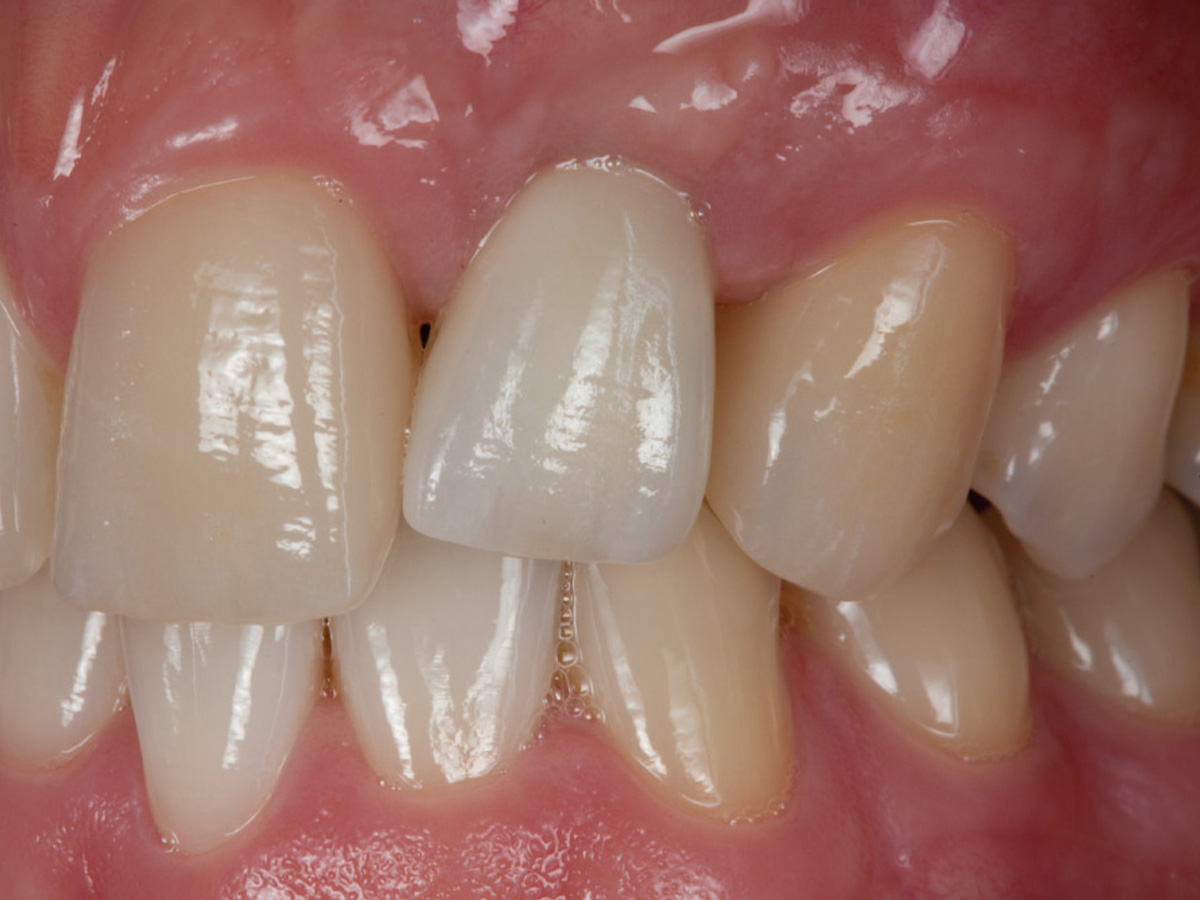

Abbildung 13

6 Monate nach vollkeramischer Versorgung.